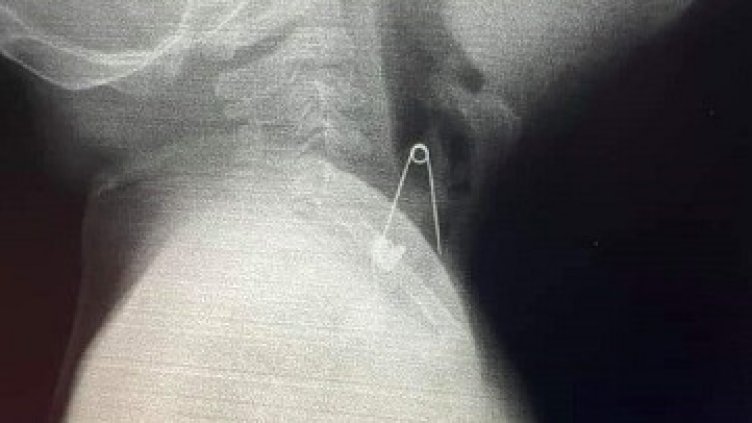

Снимка: доц. Георги Илиев

Лекари от УМБАЛ „Св. Марина“ във Варна извадиха безопасна игла от ларинкса на шестмесечно бебе. Тя била закачена на възглавничката му против уроки. Родителят, който гледал детето, се разсеял за секунда и когато се обърнал, видял как детето гълта иглата.

„Бебето веднага е доведено в болницата и лекарите извадиха иглата, като няма никакви травми за него. Съветвам обаче родителите да бъдат много, много внимателни, когато оставят децата си, особено бебетата, в близост до такива дребни предмети, защото те слагат всичко в устата си”, каза за Радио „Фокус” – Варна проф. д-р Виолета Йотова, ръководител на направление педиатрия в УМБАЛ „Св. Марина”.

Родителите трябва да са изключително внимателни, когато оставят в близост до бебета си безопасни игли или топлийки, защото малките деца слагат всичко в устата си, а това може да доведе до сериозни проблеми, добави тя.